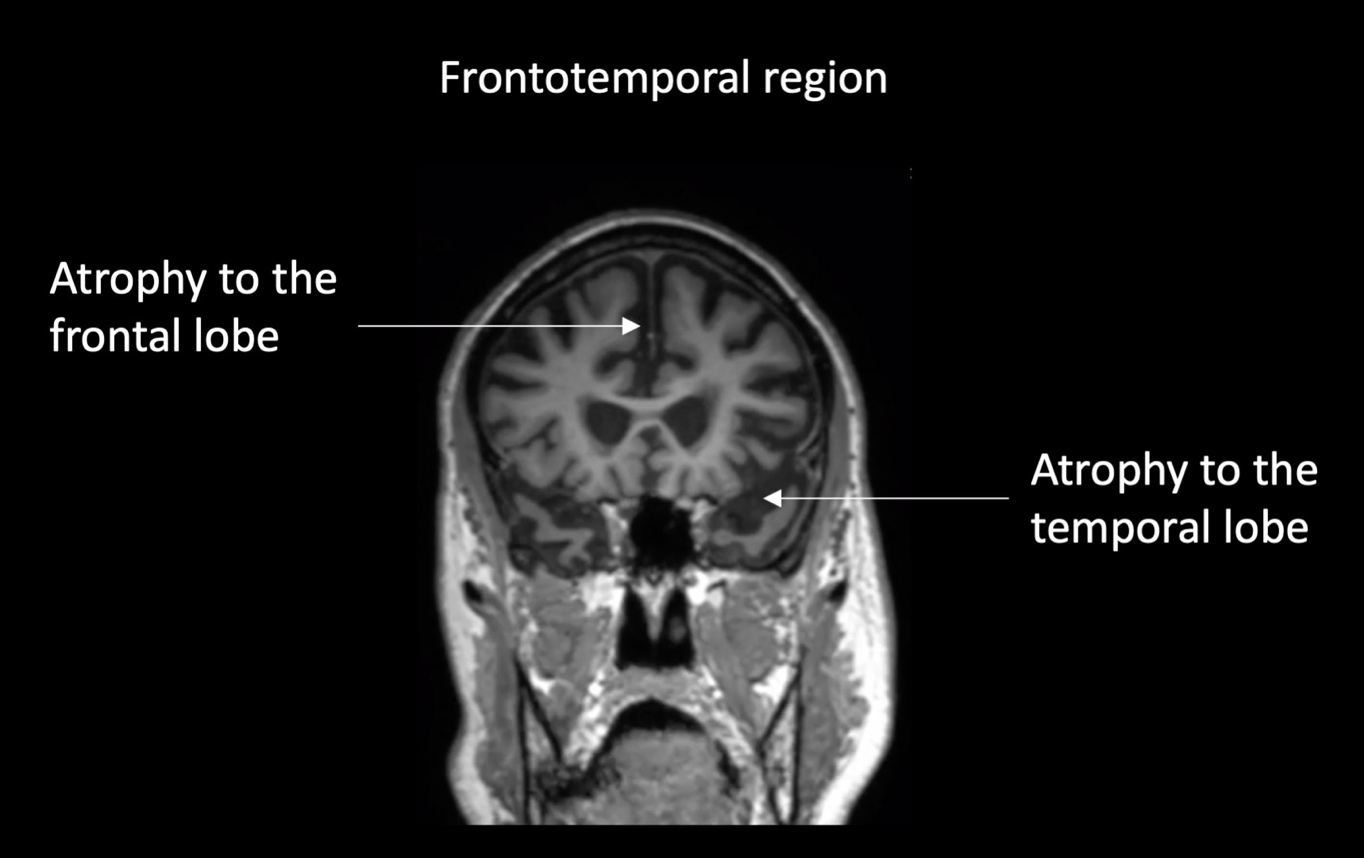

Brain scan of a person with frontotemporal dementia. Source: FRONTIER/USYD

Unlike Alzheimer's disease, which primarily affects memory, bvFTD targets the brain's frontal lobes, which govern personality and social behaviour.